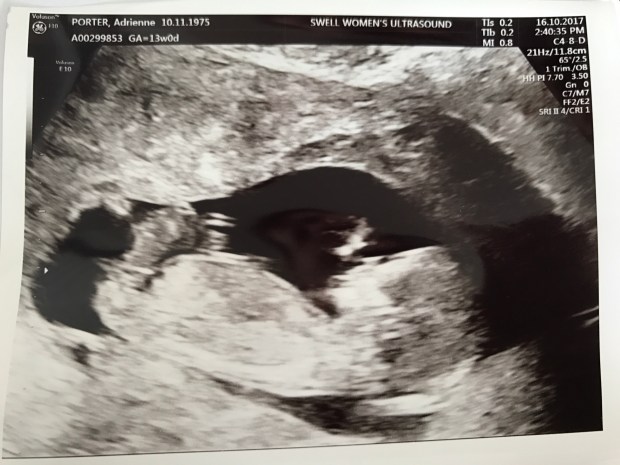

By seven weeks it’s time to go for the heartbeat scan. I hold my breath, I’m so scared. Last time we got this far only to find no heartbeat. I sit up on the gurney and nervously lay back. Dr Babies inserts the probe and brings the image up on the screen. He fiddles with the screen for a moment. ‘Ah, there we go,’ he says. ‘Heartbeat nice and strong, all looks good in there.’ We hear it’s faint thumpety thump like a tiny drum and The Vet squeezes my hand tight. Tears trickle down his cheeks. ‘It’s real,’ I whisper quietly. ‘That’s our tiny baby in there…we did it’.

It doesn’t seem truly real until I see our tiny jellybean moving on the screen four weeks later. But even then, the journey, the fear that choking feeling doesn’t stop when you get two lines. It doesn’t stop when you hear a heartbeat. It doesn’t even stop at the 13wk scan. It will only stop when I hold her teeny self in my arms.

Today we are thirteen weeks. We’ve made it through the first trimester hump that tests the very faith of every parent. We can breathe a tiny sigh of relief between takes.